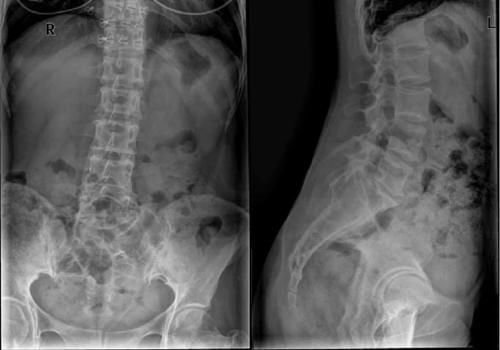

椎体|脊柱常见肿瘤及肿瘤样病变的几种影像学表现,你都见过吗?( 三 )